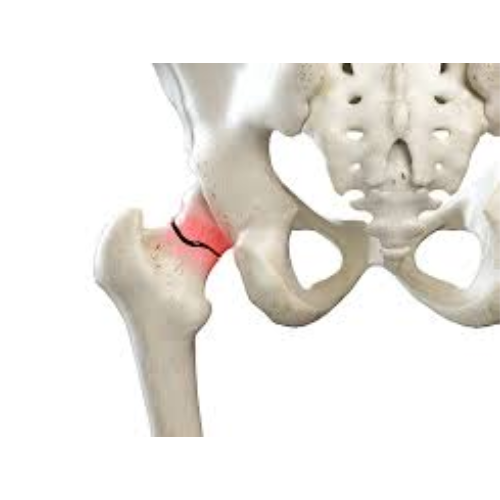

Hip Fractures

Hip fractures are serious breaks in the upper part of the thigh bone near the hip joint, most commonly caused by falls in older adults or high-impact trauma. They lead to severe pain, inability to stand or walk, and require prompt medical or surgical treatment to restore mobility and prevent complications.

Neck of Femur Fracture

A neck of femur fracture is a break in the upper part of the thigh bone just below the hip joint. It is common in older adults after a fall and can severely affect mobility and independence.

Who Needs It?

• Elderly individuals after a fall

• Severe hip pain and inability to stand or walk

• Shortened or externally turned leg

• Patients with weak bones due to osteoporosis

Benefits:

• Restores hip stability and alignment

• Enables early mobilization and walking

• Reduces complications from prolonged bed rest

• Relieves pain and improves quality of life

• Helps regain independence in daily activities

Intertrochanteric Fractures

An intertrochanteric fracture is a break in the upper part of the thigh bone between the neck of the femur and the shaft. It commonly occurs in older adults after a fall and is often associated with osteoporosis.

• Elderly individuals with a history of falls

• Severe hip pain with swelling and bruising

• Inability to stand or bear weight on the affected leg

• Leg appearing shortened or turned outward

• Stabilizes the fracture with strong fixation

• Allows early movement and walking

• Reduces risk of complications from prolonged bed rest

• Promotes proper healing and alignment

Subtrochanteric Fractures

A subtrochanteric fracture is a break in the upper thigh bone just below the hip joint, extending into the strong shaft of the femur. It may occur due to high-impact trauma in younger people or weakened bones in older adults.

• Severe hip or upper thigh pain after injury

• Inability to stand or bear weight

• Swelling, deformity, or leg shortening

• Patients with osteoporosis or those involved in accidents

• Provides strong stabilization of the fracture

• Restores proper bone alignment

• Enables gradual return to walking

• Reduces pain and risk of complications

• Supports safe and effective bone healing